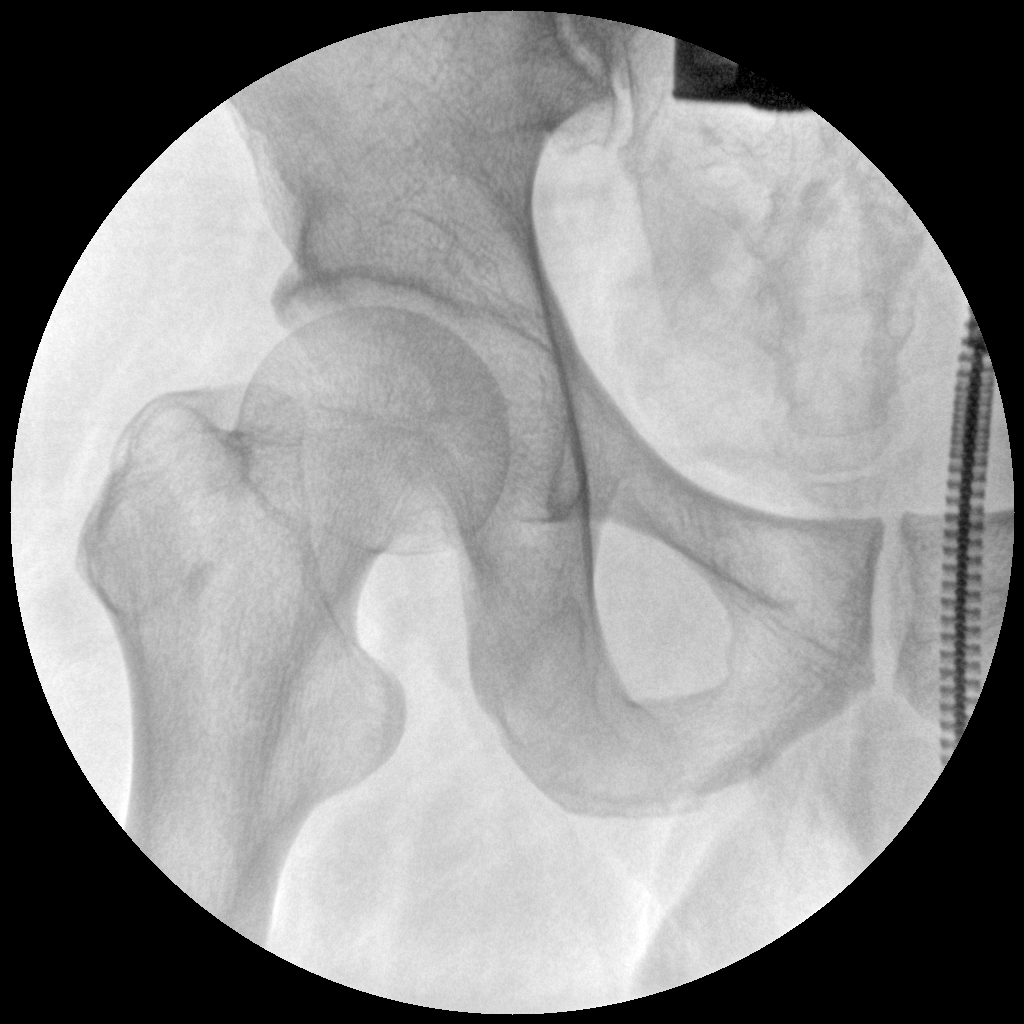

Clinical picture

临床图片